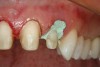

Figure 13  Preoperative view of a fixed partial denture that spanned anteriorly from tooth No. 18 to tooth No. 21. There was a minor biologic width encroachment on the distal aspect of the anterior abutment, tooth No. 21. The anterior abutment also had recurrent facial decay apical to the restorative margin and a lack of attached gingiva on the facial aspect.

Figure 13